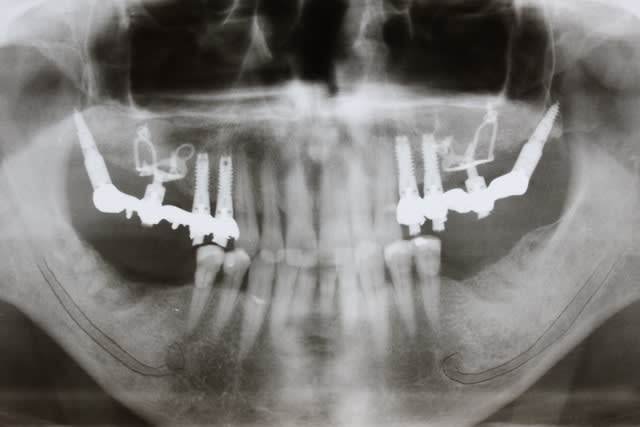

Je vous met la pano complète ainsi que des détails qui je l'espère seront suffisants pour vous faire une idée.

Les hauteurs que j'ai pu indiquer comporte aussi de la dentine infiltrée, pardonnez moi de le préciser.

Quant au bas, le patient étant content on attend une bonne cicat du haut et on s'y attaque avant d'entamer les définitifs.........